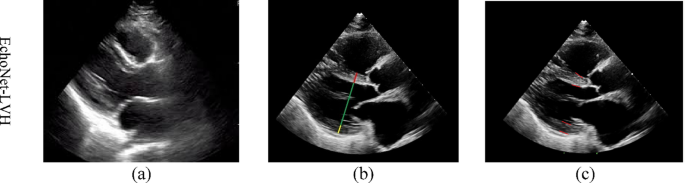

The EchoNet-LVH dataset is an open-source collection designed for the automated measurement of left ventricular wall thickness to assess for hypertrophy11. It contains 12,000 echocardiography videos in the parasternal long-axis (PLAX) view, acquired from patients as part of their routine clinical care at the Stanford cardiology clinic between 2008 and 2020. For each video, expert cardiologists have provided annotations for the end-systole and end-diastole frames, including measurements for the Interventricular Septum (IVS), Left Ventricular Internal Dimension (LVID), and Left Ventricular Posterior Wall (LVPW). The data includes the specific frame numbers for each measurement and the corresponding keypoint coordinates (X1, Y1, X2, Y2) needed for our keypoint detection task. The details of the EchoNet-LVH dataset are summarized in Table 1, and Fig. 1 shows a sample image of this dataset.